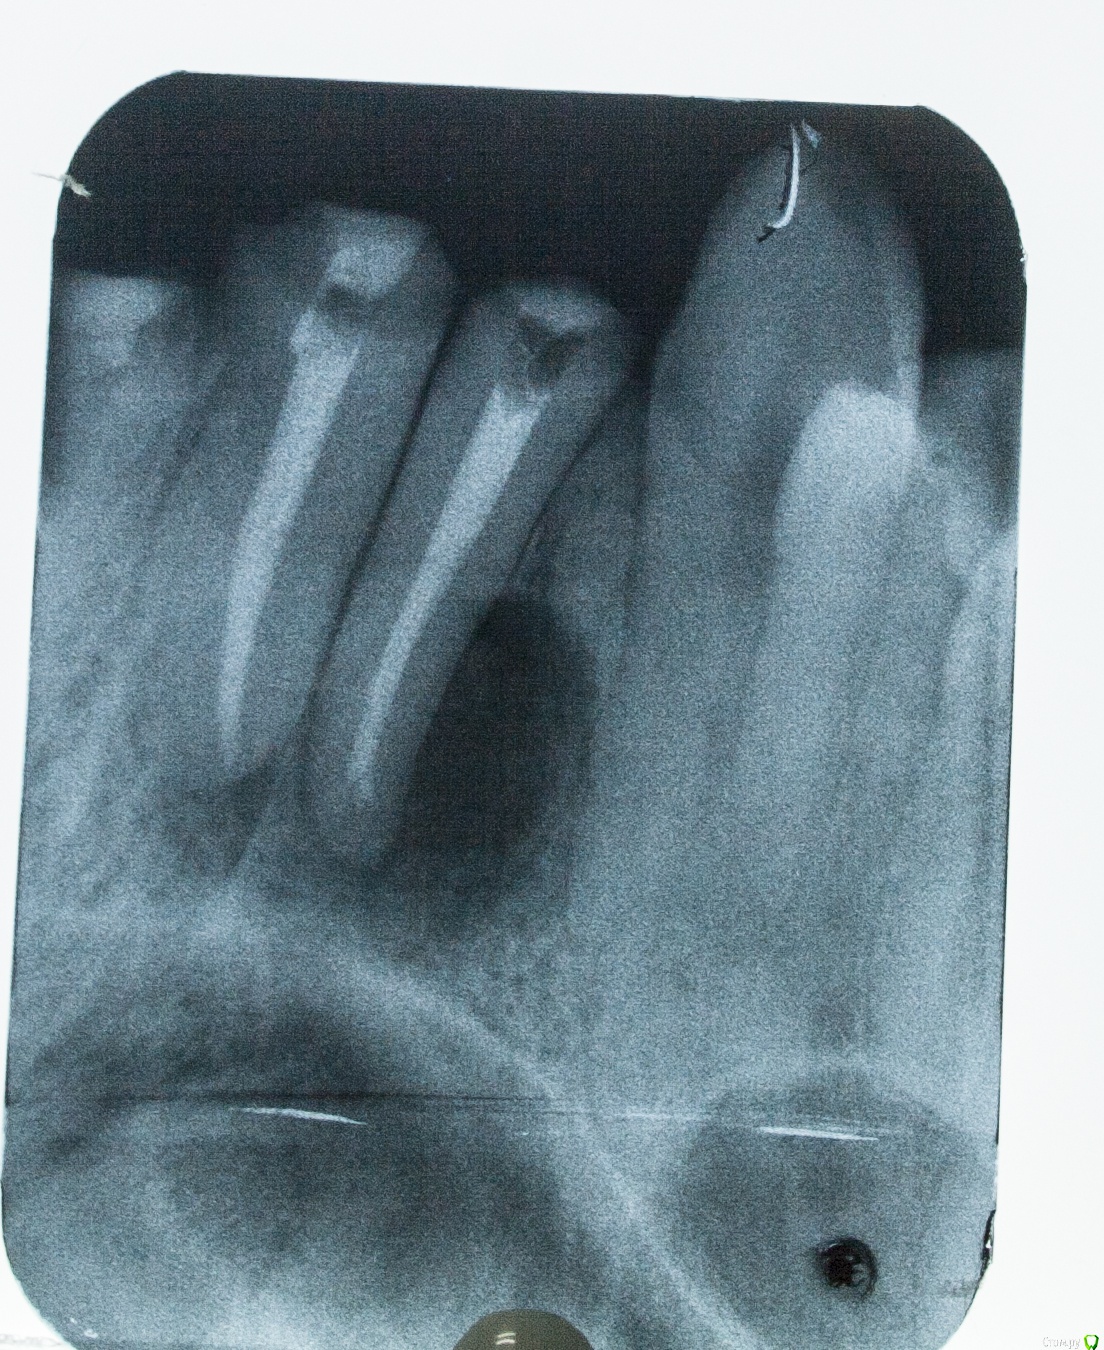

diesel87 Опубликовано 24 ноября, 2015 Поделиться Опубликовано 24 ноября, 2015 Спрошу у терапевтов, сегодня пришла пациентка полечить пульпит в 14, полечили, принесла с собой орто, посмотрел, забавная гранулема в пазухе выросла, причина видимо 16, есть подвижность 1 степени, со стороны неба отмечает периодические выбухания, которые сами проходят. Думаю ей 12 лет, не пациентке. Что скажите господа, эндо имеет смысл? http://fs5.directupload.net/images/151124/2hrfb9kp.jpg http://fs5.directupload.net/images/151124/nf6tk9pj.jpg Ссылка на комментарий

Neilrus Опубликовано 24 ноября, 2015 Поделиться Опубликовано 24 ноября, 2015 Эод может сделать чтобы понять связано или нет? Не увеен насчет того, что это можно через каналы лечить. Но я бы ради интереса попробовал, если от зуба пошло, конечно. Вот только небно немного напрягает, резорбция стенки мощная. Ссылка на комментарий

DmitrySH Опубликовано 24 ноября, 2015 Поделиться Опубликовано 24 ноября, 2015 КТ надо бы, делать эндо, но в голове держать план возможной хирургической реабилитации.14, тоже гранулема. 1 Ссылка на комментарий